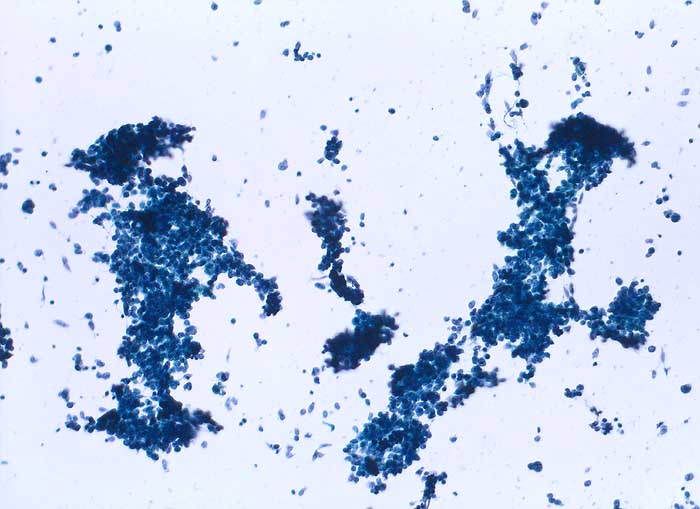

Die Tumorzellen des kleinzelligen Karzinoms erscheinen in der Übersicht eher einförmig. Bei stärkerer Vergrösserung zeigt sich aber eine deutliche Polymorphie. Die Kerne sind rundlich, eckig oder spindelig und je nach Erhaltungszustand mehr oder weniger hyperchromatisch. Der Kernhintergrund ist dunkel und das Chromatin fein dispers. Nukleolen sind meist unscheinbar. Plumpe grosse Nukleolen sprechen eher für ein grosszellig neuroendokrines Karzinom, dessen Morphologie im Übrigen mit derjenigen des kleinzelligen Karzinoms überlappt. Die Abgrenzung von einem Lymphom oder aktivierten Lymphozyten kann schwierig sein.